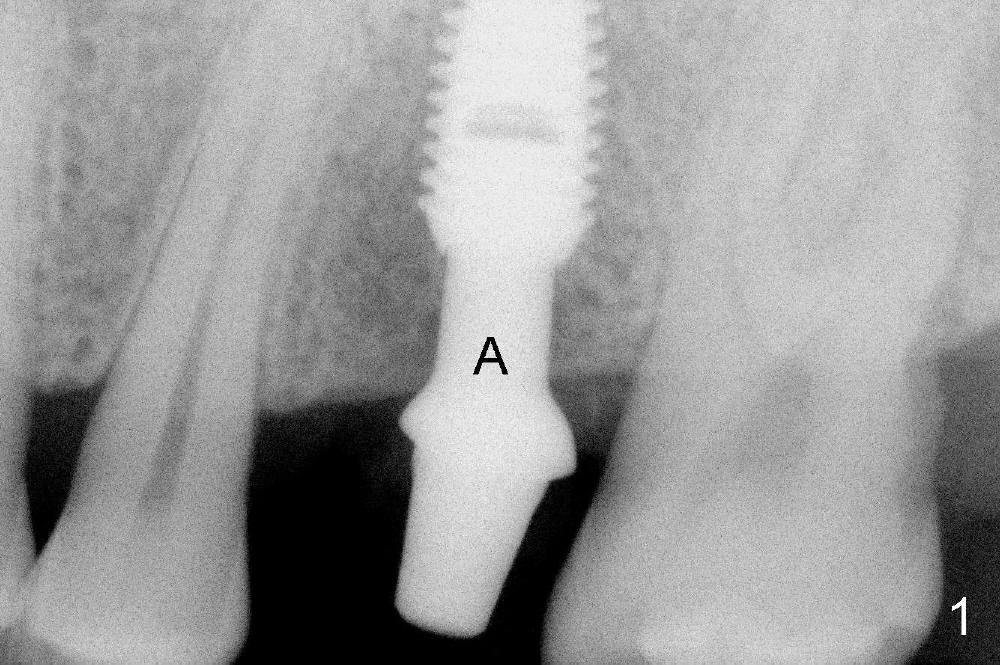

An offset shouldered abutment is inserted to an osteointegrated implant (Fig.1: A). Excess cement (Fig.2 >) is detected following intra-oral cementation of a Zirconia crown (C). The crown/abutment unit has to be removed from the implant (Fig.3). Fig.4 shows the crown/abutment unit with excess cement removed.